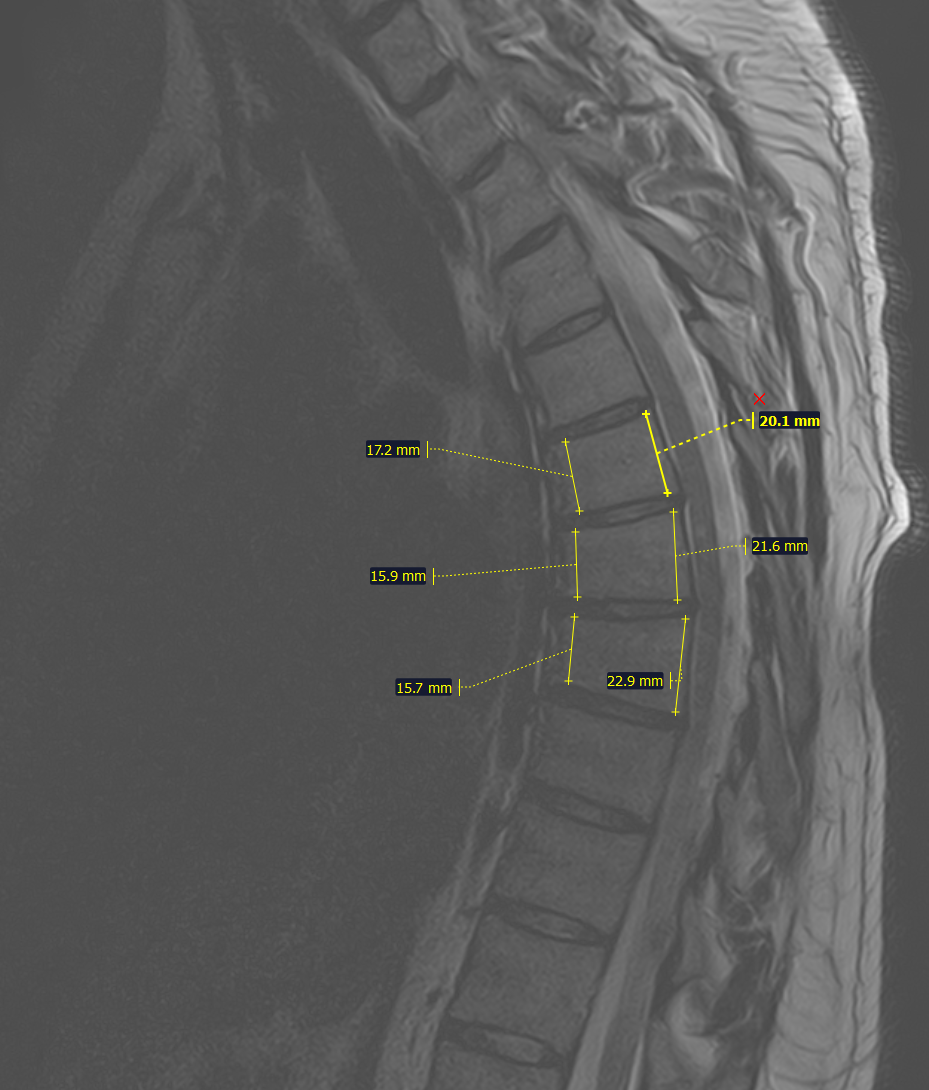

На МРТ- снижение высоты передних отделов тел Th6,7,8 позвонков(клиновидная деформация).

На Р-грамме грудного отдела позвоночника(стоя) в боковой проекции, визуализируется гиперкифоз грудного отдела позвоночника 4 ст. по Коббу. Аналогично с данными МРТ , снижение высоты передних отделов тел Th6,7,8 позвонков(клиновидная деформация).

Итоговый диагноз: Патологический гиперкифоз грудного отдела позвоночника 4 ст. по Коббу. Клиновидная деформация тел Th6, Th7, Th8 позвонков, как следствие перенесенной остеохондропатии, соответствует болезни Шейермана-Мау.S-образный сколиоз 2ст.Остеохондроз грудного, поясничного отделов позвоночника.